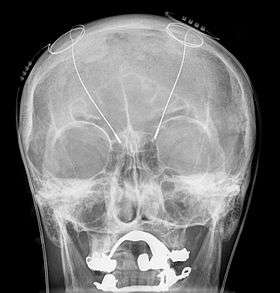

All three components are surgically implanted inside the body. Lead implantation may take place under local anesthesia or with the patient under general anesthesia ("asleep DBS") such as for dystonia. A hole about 14 mm in diameter is drilled in the skull and the probe electrode is inserted stereotactically. During the awake procedure with local anesthesia, feedback from the patient is used to determine optimal placement of the permanent electrode. During the asleep procedure, intraoperative MRI guidance is used for direct visualization of brain tissue and device.[15] The installation of the IPG and extension leads occurs under general anesthesia.[16] The right side of the brain is stimulated to address symptoms on the left side of the body and vice versa.